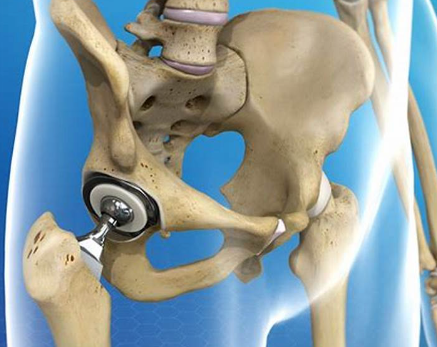

고관절 치환술(Total Hip Arthroplasty)

적응증: 고관절 치환술은 고관절 골관절염, 류마티스 관절염, 무혈성 괴사 또는 고관절 골절이 있는 개인에게 일반적으로 수행됩니다.

절차: 고관절 치환술 중 손상된 고관절의 볼-소켓 구성 요소를 인공 부품으로 교체합니다. 이 절차는 다양한 수술적 접근법을 사용하여 수행될 수 있습니다.

혜택: 고관절 치환술은 통증을 완화하고 고관절 기능을 회복하며 환자가 독립성과 이동성을 회복할 수 있도록 해줍니다.

- 임플란트 배치: 보철 관절 표면을 포함한 인공 관절 구성 요소는 시멘트 또는 압입 기술과 같은 특수 재료를 사용하여 제자리에 고정됩니다.